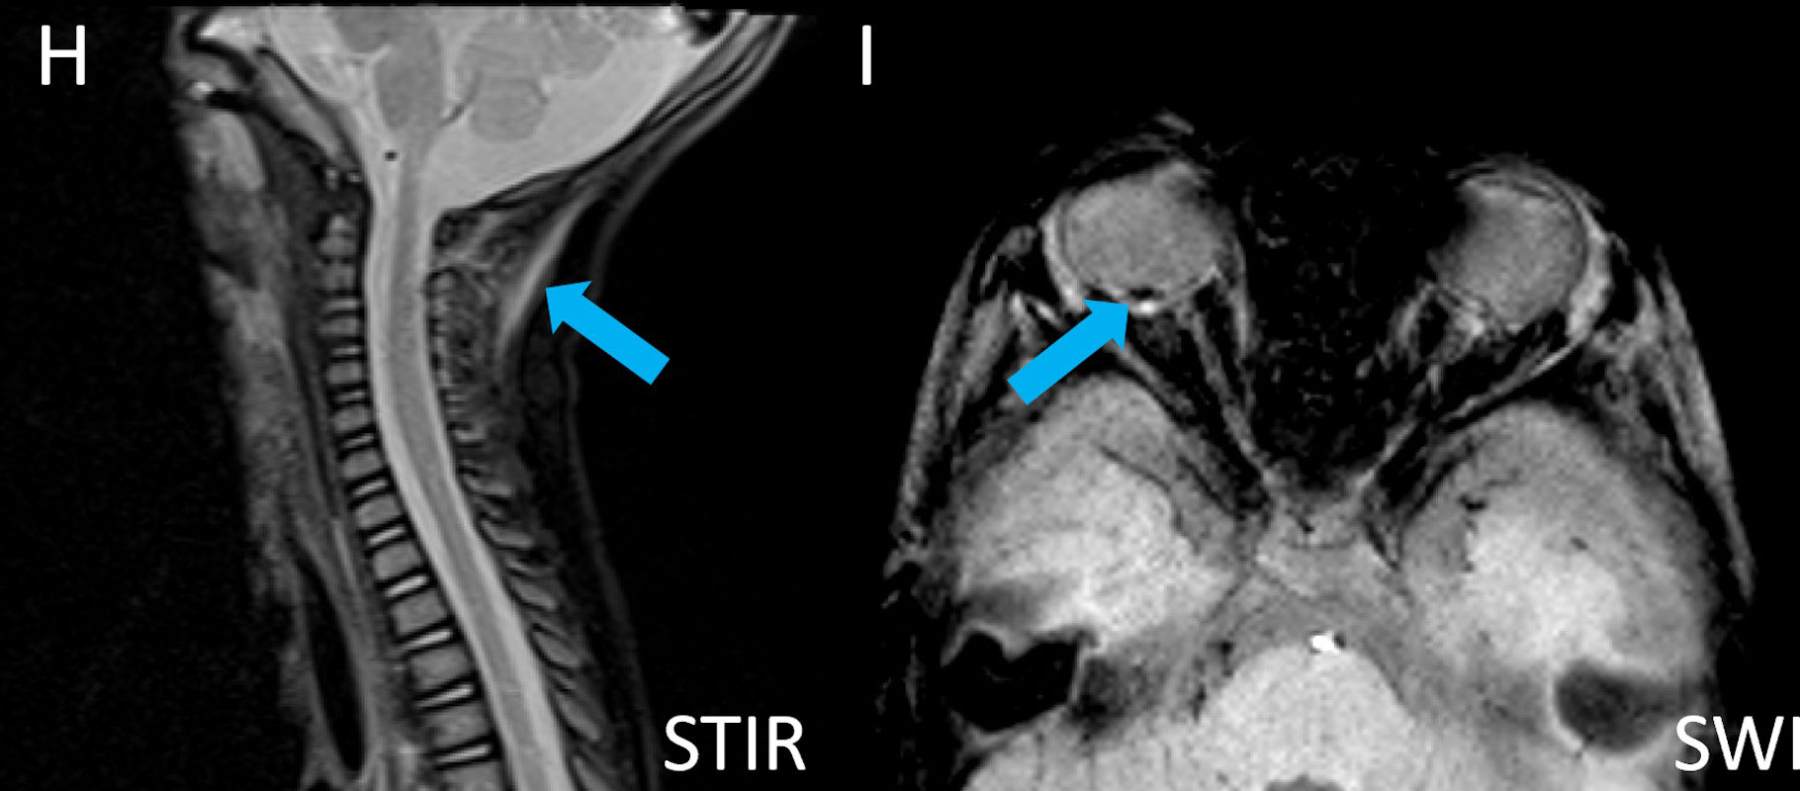

- H) Nukal bağda yaralanma lehine T2 sinyal artışı

- Spinal yaralanmalar : Sanılandan daha yaygındır ve olguların yaklaşık %30-40’ında görülür. Genellikle gözden kaçar. En sık saptanan bulgular servikal spinal bağ yaralanmaları ve spinal subdural hematomdur.